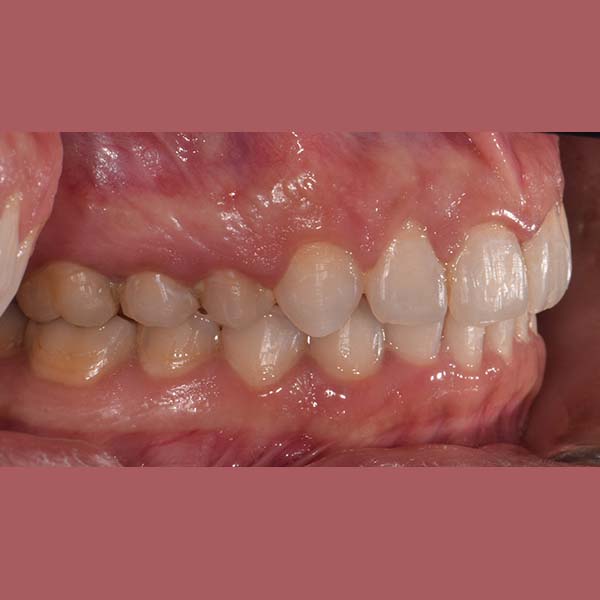

BEFORE

This lady visited me complaining that her upper teeth cover the lower ones excessively.

Examination revealed a severe deep bite, covering almost all parts of the lower teeth, in addition to a severe backward tilt in her upper front teeth, which affected the beauty of her smile.

Fortunately, this woman did not suffer from problems in her joint before the date of her visit to the clinic, Since these cases usually persist for a long time, causing pain and problems in the joint, (due to the patient’s need to open his mouth widely, each time he wants to free his lower jaw from the upper teeth)